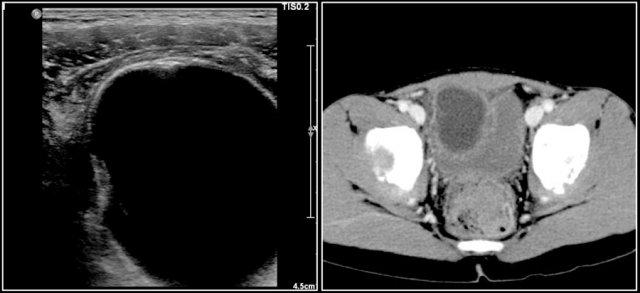

Đây là hình ảnh CT của một bé gái 13 tuổi biểu hiện với khối vùng bụng dưới.

Đây là một khối u vừa có thành phần nang vừa có thành phần đặc, kèm một số vôi hóa.

Các thành phần đặc không đồng nhất.

Khối u được phẫu thuật cắt bỏ và giải phẫu bệnh cho thấy u quái có thành phần ác tính, kèm di căn hạch bạch huyết.